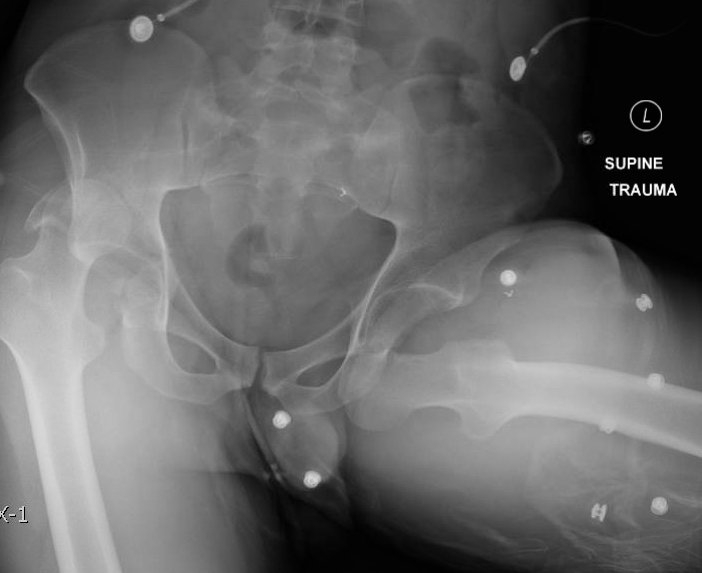

The initial radiograph of the pelvis revealed bilateral hip dislocations. Small bony fragments were noted in the right hip joint, suggestive of an underlying fracture. The sacroiliac joints and the pelvic ring were intact. In the emergency department, bilateral hip reductions were performed using the Captain Morgan technique.1 The post-reduction film showed reduction of the bilateral hip dislocations with extensive comminuted and displaced fractures of the right and left acetabula.